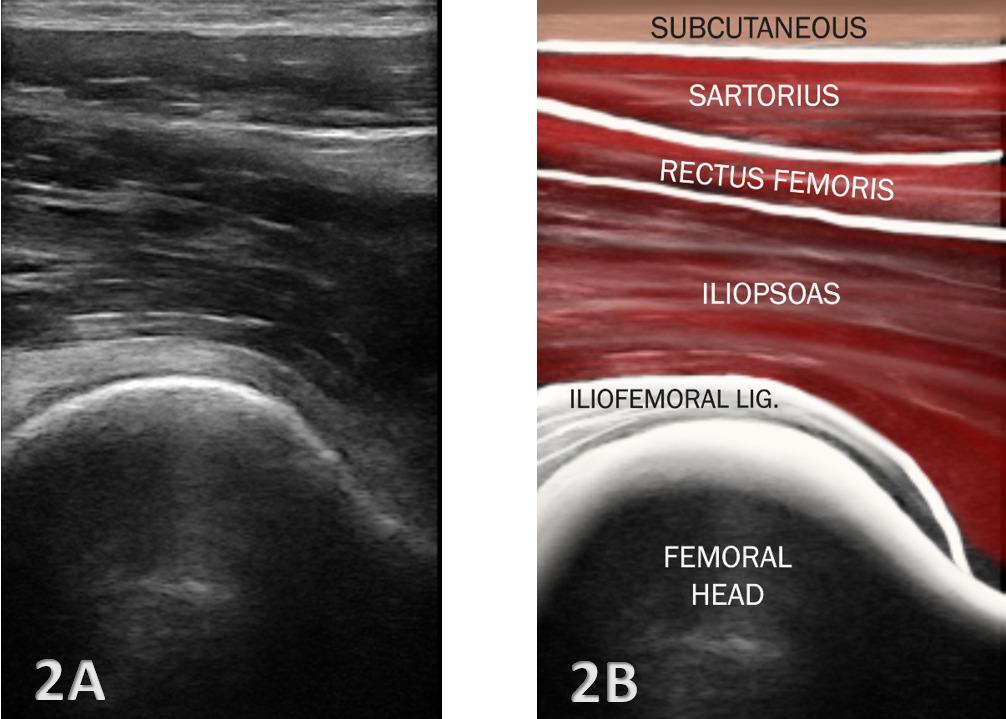

26. Ekstrand J, Lundqvist D, Davison M, D’Hooghe M, Pensgaard AM. Communication quality between the medical team and the head coach/manager is associated with injury burden and player availability in elite football clubs. Br J Sports Med 2019;53(5):304-308. doi:10.1136/ bjsports-2018-099411

27. Little C, Lavender AP, Starcevich C, et al. Understanding fear after an anterior cruciate ligament injury: a qualitative thematic analysis using the common-sense model. Int J Environ Res Public Health 2023;20(4). doi:10.3390/ijerph20042920

Solie B, Carlson M,

C,

Oh, My Quad: A Clinical Commentary And Evidence-Based Framework for the Rehabilitation of Quadriceps Size and Strength after Anterior Cruciate Ligament Reconstruction. IJSPT. 2024;19(12):1600-1628. doi:10.26603/001c.126191

Braidy

Solie1 a , Mitchell Carlson2 , Christopher Doney1 , Michael

Kiely

3 , Robert LaPrade4

1 Physical Therapy, Twin Cities Orthopedics, 2 Bioengineering Lab, Twin Cities Orthopedics , 3 Sports Science, Twin Cities Orthopedics, 4 Orthopedic Surgery, Twin Cities Orthopedics